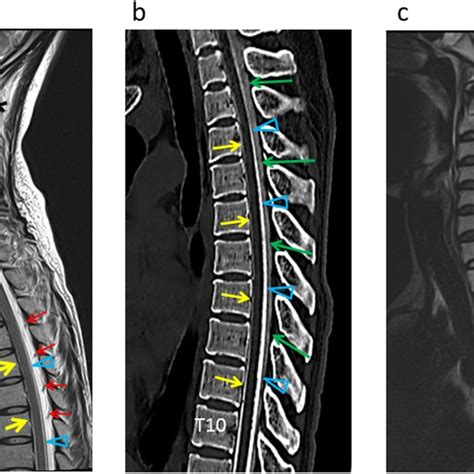

Preoperative CT images showed the formation of a disc-osteophyte ...

Preoperative T2-weighted sagittal magnetic resonance imaging clearly ...